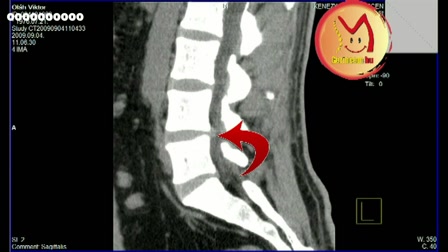

Autód vagy a gerinced?

Autód vagy a gerinced, neked mi a fontosabb?